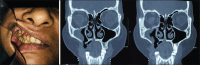

Rationale: The successful utilisation of three dimensional (3D) techniques in engineering a titanium patient specific implant (PSI) for a patient who underwent hemimaxillectomy following post COVID mucormycosis infection.

Patient concerns: Issues related to problems associated with resection following mucormycosis, such as occlusal function, aesthetics and facial asymmetry.

Diagnosis: The patient affected by mucormycosis was left with Aramany class 1 and Cordeiro type II sub total maxillectomy defect.